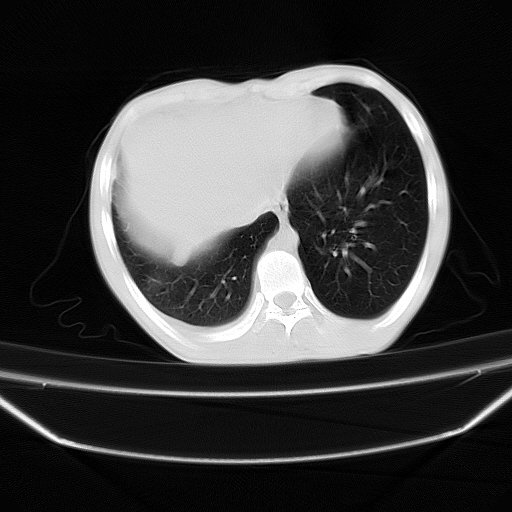

以下是引用zjzjr在2008-7-20 12:57:00的发言:[br]考虑为生殖源性肿瘤(内胚窦瘤),侵袭性胸腺瘤可能性大;右侧少量胸腔积液。

以下是引用xinliheng001在2008-7-20 21:17:00的发言:[br]右纵隔巨大分叶状软组织均质密度肿块,右上肺叶受压明显,纵隔右移、胸膜受累有少量积液和结节样增厚。应增强扫描一定会有更具诊断价值的信息。

以下是引用xinliheng001在2008-7-20 21:17:00的发言:[br]右纵隔巨大分叶状软组织均质密度肿块,右上肺叶受压明显,纵隔右移、胸膜受累有少量积液和结节样增厚。应增强扫描一定会有更具诊断价值的信息。